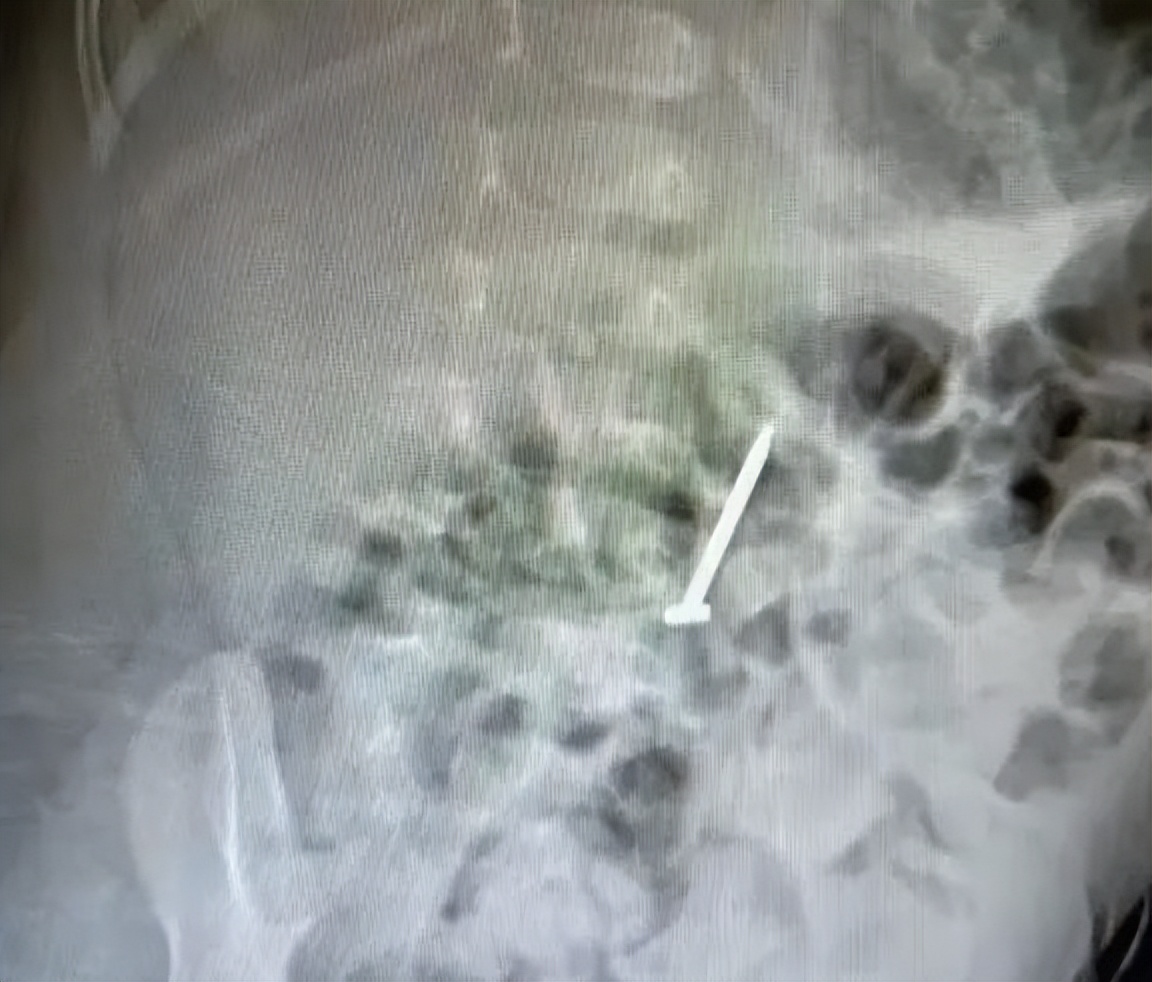

据这位妈妈回忆,当日,奶奶带着11个月大的孙女乐乐(化名)在阳台玩耍。就在转身的瞬间,奶奶隐约看到孙女把一个东西塞进了嘴里。看着阳台上散落的几枚装修时遗落的铁钉,奶奶心里急了:会不会把钉子吞进了肚子?奶奶赶紧把这事告诉了孩子爸妈。爸爸妈妈一听,不敢马虎,立即带着孩子到了当地医院。胸片显示,在乐乐的中腹部有一钉状致密影,长径约31.1mm,尖端位置朝上。

急诊科医生沈丹萍查看了宝宝的腹部平片报告,发现确有一枚长长的钉子,就在孩子腹部。

胃镜和胸片检查显示,乐乐体内的铁钉已经随着消化道进入了小肠,随着小肠的蠕动正往大肠方向移动。